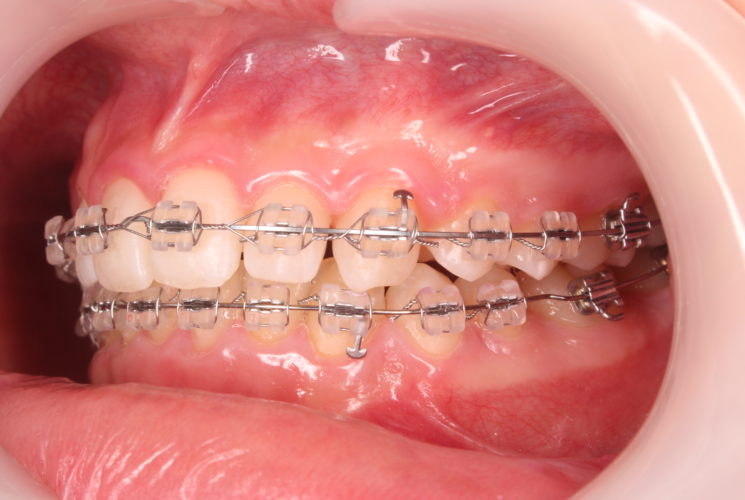

上下の装置が付いた状態です。

ミラー側方観(左側)

だいぶ上顎前歯が圧下され、下の前歯とのスペースが出来てきたので、矯正装置を装着しました。

ここから下顎前歯も圧下(下方に押し下げる)を開始し、歯軸(歯の傾き)等の改善も行っていきます。